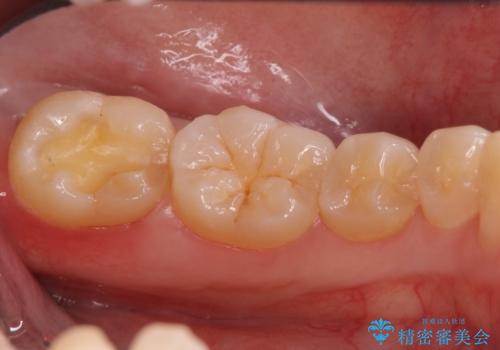

奥歯の虫歯 セラミックインレーでの治療

- 下の奥歯の黒ずみが気になるとのことで来院されました。

検査の結果咬む面に虫歯があることがわかりました。

削る前は小さな虫歯に見えますが、歯の中で進行しつつある虫歯でした。

虫歯が大きくなると必要な治療が増えてえしまうため早期発見、早期治療を行うことが大事になってきます。